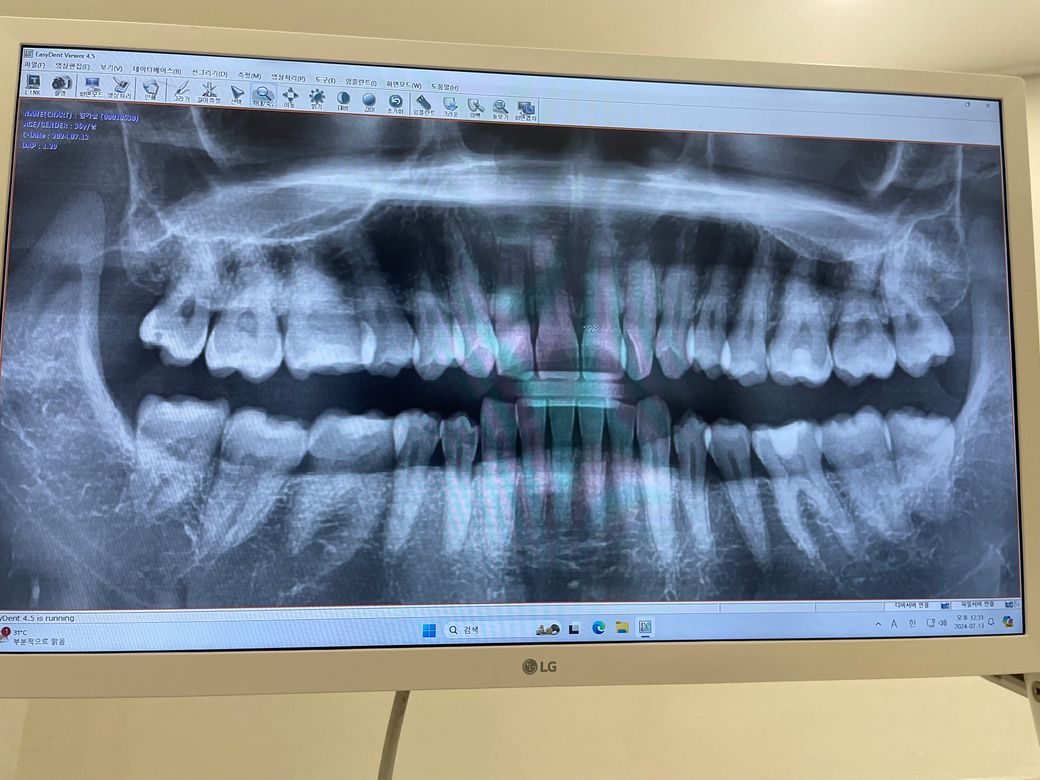

37곱 나이애 이정도면 치아괜찮을까요 ?

나이37곱 입니다 어제 스케일링 하고 왔는데요 엑스레이 처음 찍어보고 의사 선생님이 엑스레이 보고 별다른 애기 없으 시더라고요 저정도면 충치나 치아 상태 어는 정도 일까요 제 나이애 저정도면 치아 상태 괜찮은가요 ?

사진으로만 봤을 경우에는 크게 문제가 없이 관리가 잘되어 있는것으로 보입니다.

현재 사진에서는 특별한 소견이 보이지는 않습니다. 다만 정확한 진단을 위해서는 해당 사진이 아닌 치아 개별적인 사진이 필요하며 구강 내 임상 검사도 같이 해보아야 합니다. 별다른 말씀을 하지 않았다면 주기적으로 치과를 방문하여 정기적인 검진을 하시면 될 것으로 보입니다.

특별히 나쁘지는 않아보입니다. 다만 사랑니가 있는 것들은 나이가 젊을 때 빼는 것이 빼기 쉽습니다.

1. 잇몸높이가 많이 낮아져있지 않습니다

2. 뚜렷이 보이는 충치는 없습니다

3. 사랑니가 바르게 나와 빼지는 않아도 되나 관리를 잘해서 충치가 생기지 않도록 해야 합니다

충치여부는 직접 검사를 해봐야 알수 잇을꺼 같고 잇몸이나 전체적은 부분은 크게 문제가 잇어 보이진 않아 보입니다.